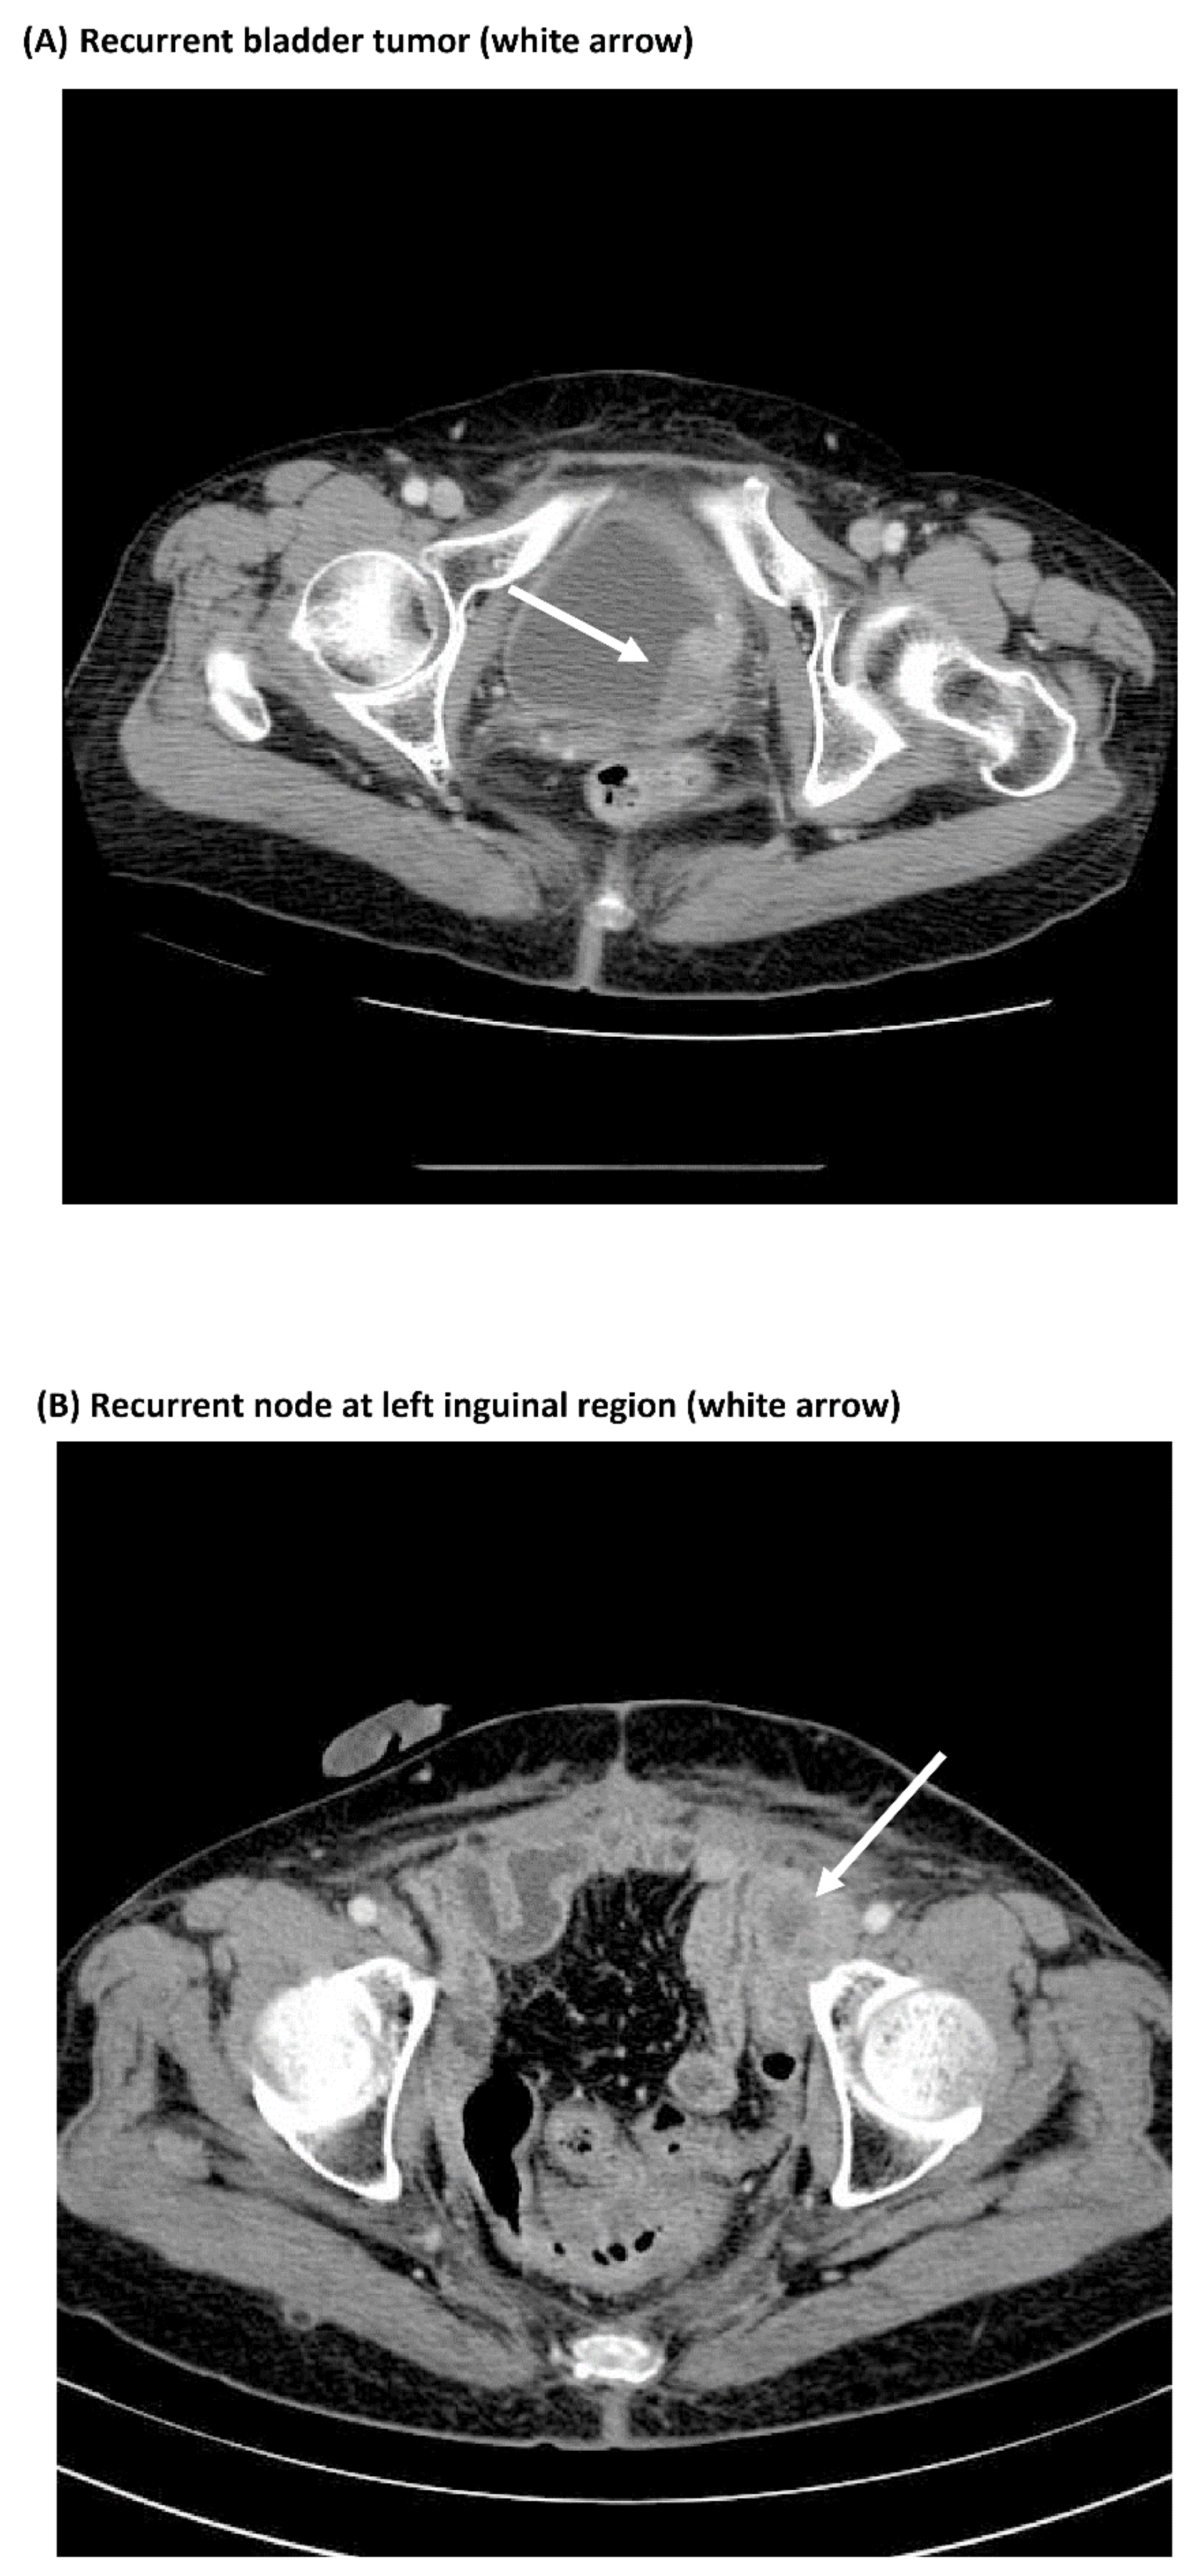

3.3. Comparisons of Immunostaining of NFκB between Pre-Treatment Samples and Recurrent Samples